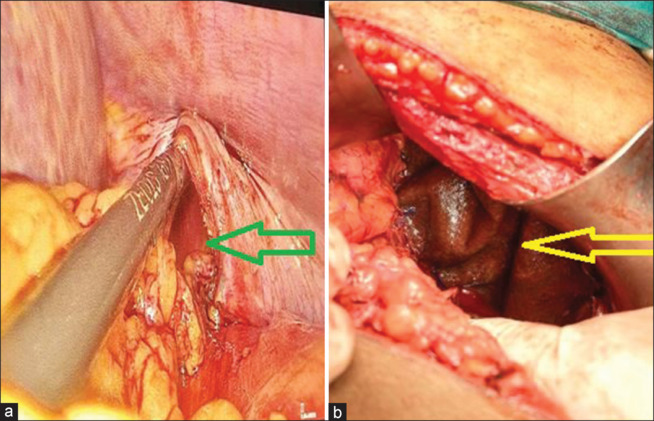

先天性膈疝(CDH)和获得性膈疝(ADH)继发于膈肌无力或开口。两者都是内疝的类型。这种异常的范围可以从膈肌后缘的一个小缺陷到整个膈肌的丧失。CDH通常导致肺发育不全,伴有肺动脉高压和不成熟,以及心功能障碍。在ADH中,病理生理是继发于疝出及其压力效应。我们报告了两例自发性ADH (SADH)。自发性获得性膈肌破裂可发生在运动、咳嗽、分娩后,甚至在没有任何明显的前期事件的情况下。尚不确定SADH是由膈肌先前存在的薄弱区域引起的,还是由于剧烈运动时肌肉协调性的丧失,或两者兼而有之。这是一种潜在致命的外科急诊,需要在适当的临床环境中进行高指标的临床判断。SADH通过压迫肺来机械地起作用。这是一个罕见的实体。本病例系列和回顾简要说明自发性膈疝的发生、诊断和治疗。

Congenital diaphragmatic hernia (CDH) and acquired diaphragmatic hernia (ADH) are secondary to a weakness or opening in the diaphragm. Both are types of internal hernia. The abnormality can range from a minor defect in the posterior edge of the diaphragm to the entire loss of it. CDH usually leads to lung hypoplasia associated with pulmonary hypertension and immaturity, as well as cardiac dysfunction. In ADH, pathophysiology is secondary to herniation and its pressure effects. We report a series of two cases of spontaneous ADH (SADH). Spontaneous acquired rupture of the diaphragm can occur after exercise, coughing, labor (delivery), or even without any significant preceding event. It is uncertain if SADH is caused by a preexisting weak region in the diaphragm, a loss of muscle coordination during vigorous exertion, or both. It is a potentially fatal surgical emergency requiring a high index of clinical judgment in the appropriate clinical setting. SADH acts mechanically by compressing the lung. It is an infrequent entity. This case series and review concisely illustrate the genesis, diagnosis, and treatment of spontaneous diaphragmatic hernia.